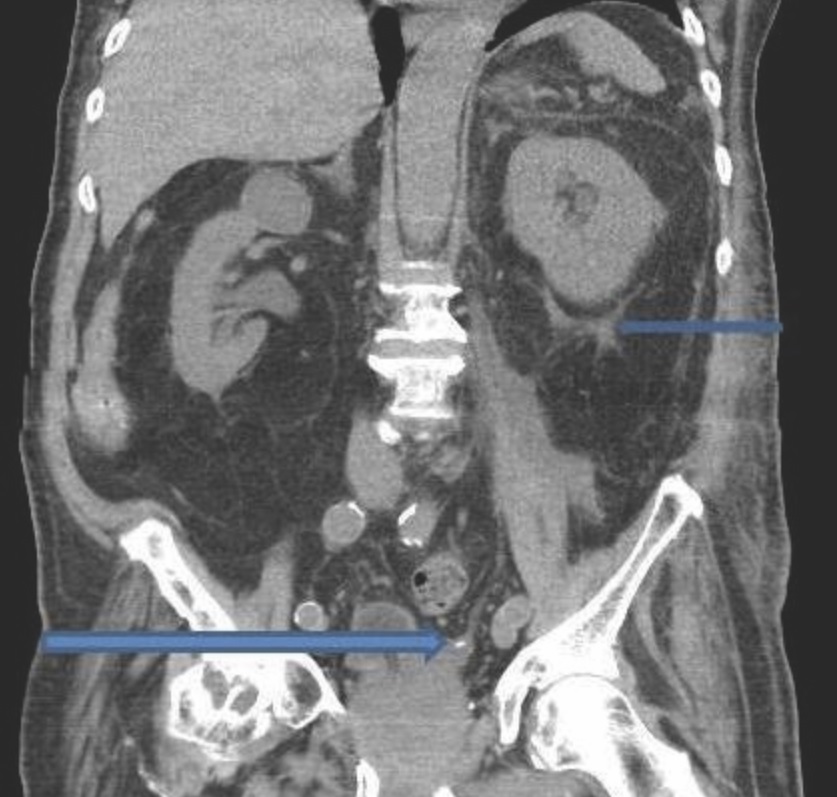

Low intake of fluids, excessive dehydration, urinary tract infections, and family history can lead to the aggressiveness of the disease. CT scan, ultrasound, and abdominal x-ray are used to diagnose calyceal stone. The gold standard test is a CT scan but in emergency conditions, ultrasound will be the best and prompt choice.